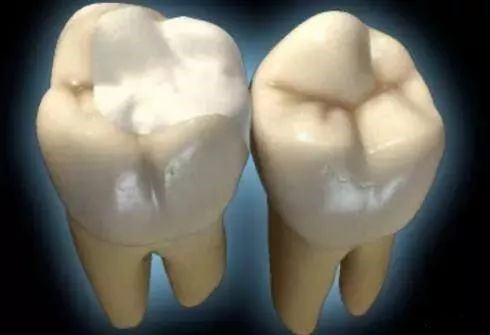

“嵌体顾名思义就是一种嵌入牙体内部的修复方法是为牙齿量身定做的修复体,通过黏合剂将其黏在有缺损的牙齿上。”由于嵌体在形态、硬度等各方面与牙齿吻合度很好,所以,它不仅解决了牙齿缺失部分容易变大的难题,也减轻了患者频繁补牙的痛苦。

7、嵌体的另一个优势是因为它的整个制作过程是在口外完成的,所以它还可以很好的恢复原来牙齿的外形,恢复原来牙齿的咀嚼效率,而这一点是传统补牙方法无论如何都无法比拟的。